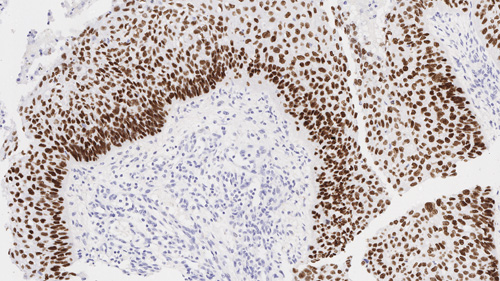

Squamous cell carcinoma of lung: Immunohistochemistry staining of p40. p40: clone BC28

p40

Antecedentes de antigénio p40 (Delta Np63) é um produto truncado do p63. É normalmente expresso na camada celular basal ou progenitora de células basais, do epitélio estratificado da próstata, bem como células mioepiteliais da mama e glândulas salivares, e citotrofoblastos na placenta, e apresenta um padrão de coloração nuclear com IHC. Entre os inúmeros neoplasmas com resultados positivos para p40, carcinomas de células escamosas de origem pulmonar e não pulmonar podem ser identificados a partir de outras malignidades.